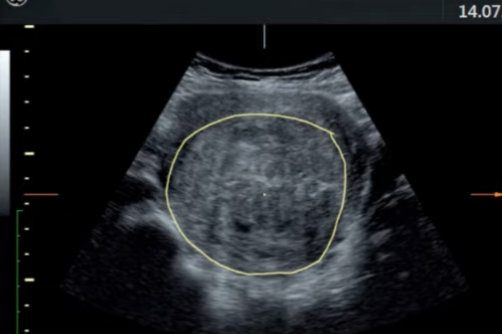

她的月经是正常的 这是一个叫Selva的医生在网上发表的第一例HIFU治疗子宫肌瘤的故事 《My first HIFU patient with fibroids》 临床结果的预测